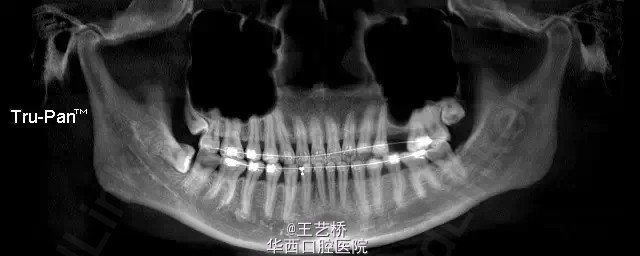

各式各样形态的上颌窦(一)

在进行上颌后牙区种植手术时,上颌窦形态是我们需要考虑吧的重要因素之一。今天收集了众多上颌窦的影像片,供大家交流学习。